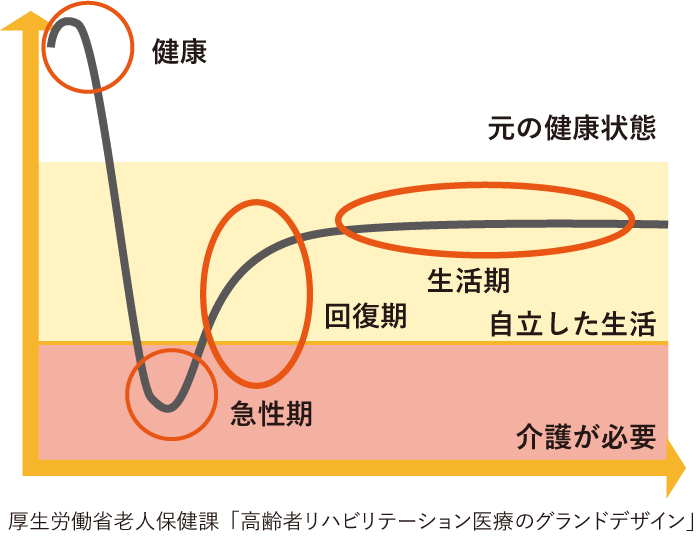

ご高齢の患者さまは、骨粗鬆症等により軽度の転倒などでも骨折する場合があります。一度骨折すると再骨折する可能性が高まり、脆弱性骨折により健康度が悪化します。なかでも大腿骨近位部骨折や椎体骨折は、以前の健康状態に回復することは困難になります。また、骨折後の死亡率が高くなるデータが確認されています。

下の図は、大腿骨近位部骨折をすると6年の間に40%近くの患者さまが亡くなっていることを示しています。

これらの報告は、骨折による活動性の低下から嚥下機能を含む筋力低下・環境の変化による認知症の発症や増悪・せん妄が出現する可能性があることや、心不全・肺・脳血管障害・全身の感染症などにより命を脅かす合併症を起こす可能性があることを示しています。早期手術が予後にはよいと知られていることから、当院では早期に手術を行うことに積極的に取り組んでおります。

脆弱性骨折は繰り返すことが多く、二次性骨折を予防することは極めて重要と考え、骨粗鬆症の治療にも力を入れています。種々の骨代謝マーカーの測定や高解像度末梢骨用定量的コンピュータ断層撮影装置(HR-pQCT)撮影も可能で、骨の微細構造を明らかにし、必要時には実際の治療に取り入れています。多職種(医師、看護師、社会福祉士、薬剤師、管理栄養士、理学療法士、作業療法士、言語聴覚士など)によるチーム医療を積極的に構築し、各職種の専門性を重視した診療を行っています。

また、退院後においても定期的に継続して健康状態を確認しております。